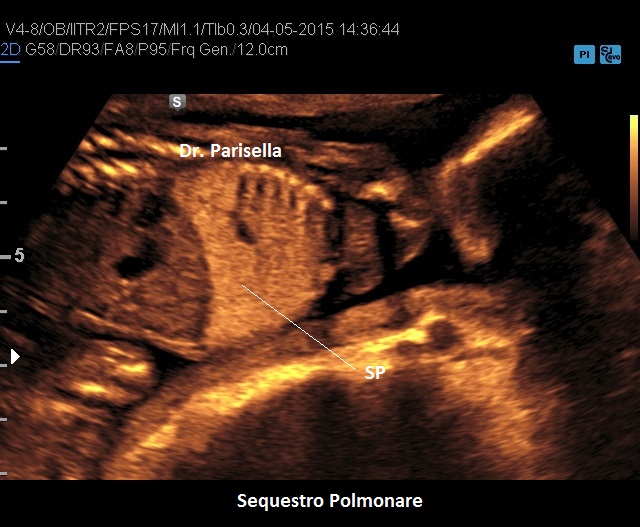

Il Sequestro Polmonare è costituito da un'area di parenchima polmonare che non è in comunicazione con l'albero tracheo-bronchiale ed è tributaria della circolazione sistemica e non polmonare. E' una lesione monolaterale, localizzata nella maggior parte dei casi al lobo inferiore del polmone sinistro. Ne esistono due varianti:

• extra-lobare: è una forma più rara ed è quella classicamente diagnosticata in epoca prenatale; nel 90% dei casi è sopra-diaframmatica, nel 10% è sotto-diaframmatica. Caratteristicamente presenta un vaso afferente a partenza dall'aorta toracica o addominale.

Diagnosi ecografica

Si presenta come una lesione iperecogena localizzata più frequentemente al lobo inferiore del polmone sinistro, più raramente in sede sottodiaframmatica. Al Color-Doppler si evidenzia il vaso afferente a partenza dall'aorta toracica o addominale.